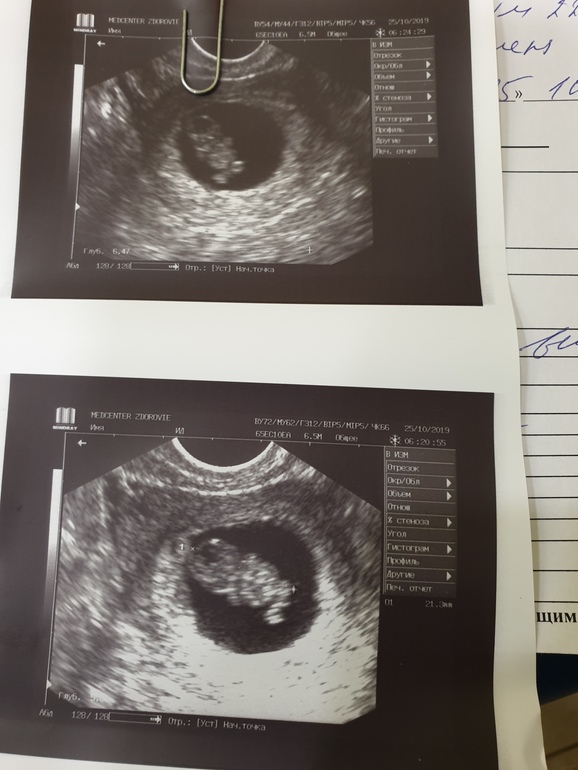

Всё о нашей беременностиДевчёнки сегодня была на узи срок ставят 9 недель как то они считают незнаю у меня меньше выходила..так вот

тамм человечек уже блин как же это волнительно🤩🤩🤪🤪от радости и про токсикоз забыла ,говорятвсе соотведствует норме ..ктр 21..мж 4.6...сб+170..хорион 40 ,как думаете размеры норм ??а то мало ли ...а так раслаблюсь на три недели до скрининга

У меня такие же фотки, 9 недель + 1 день)) КТР 24 мм, насколько помню.